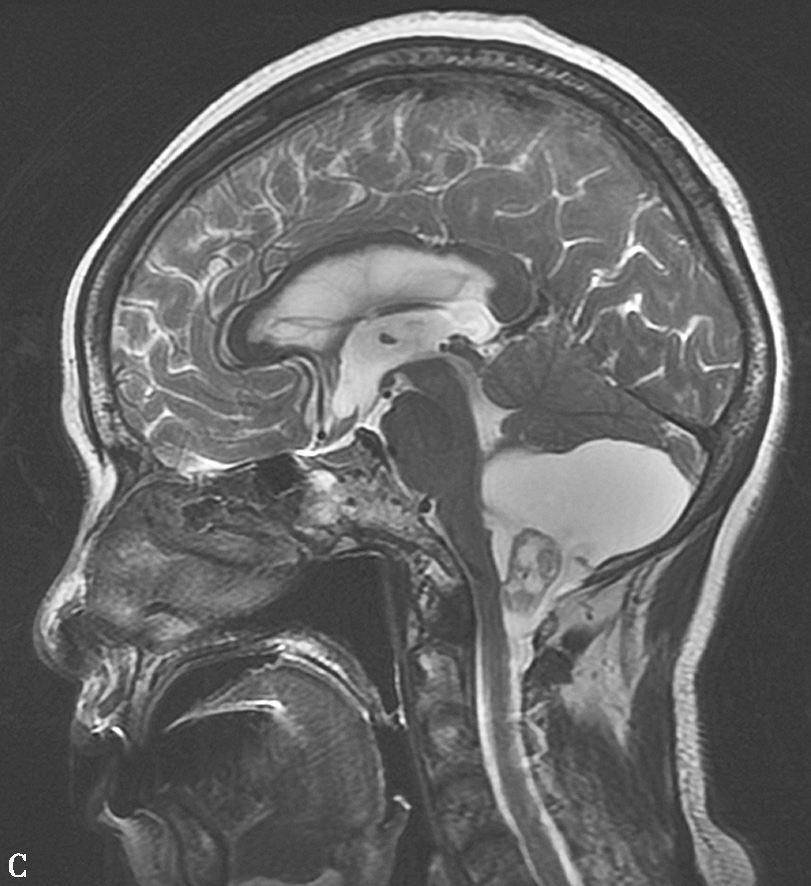

图1-12 血管母细胞瘤

图1-12 血管母细胞瘤(续)

C.T 2 WI矢状位;D.T 1 WI增强,示小脑蚓部见一囊性肿块,其内囊液呈长T 1 、长T 2 液性信号,囊壁有卵圆形等信号结节,呈“大囊伴小附壁结节”表现,增强扫描壁结节显著强化,囊壁不强化